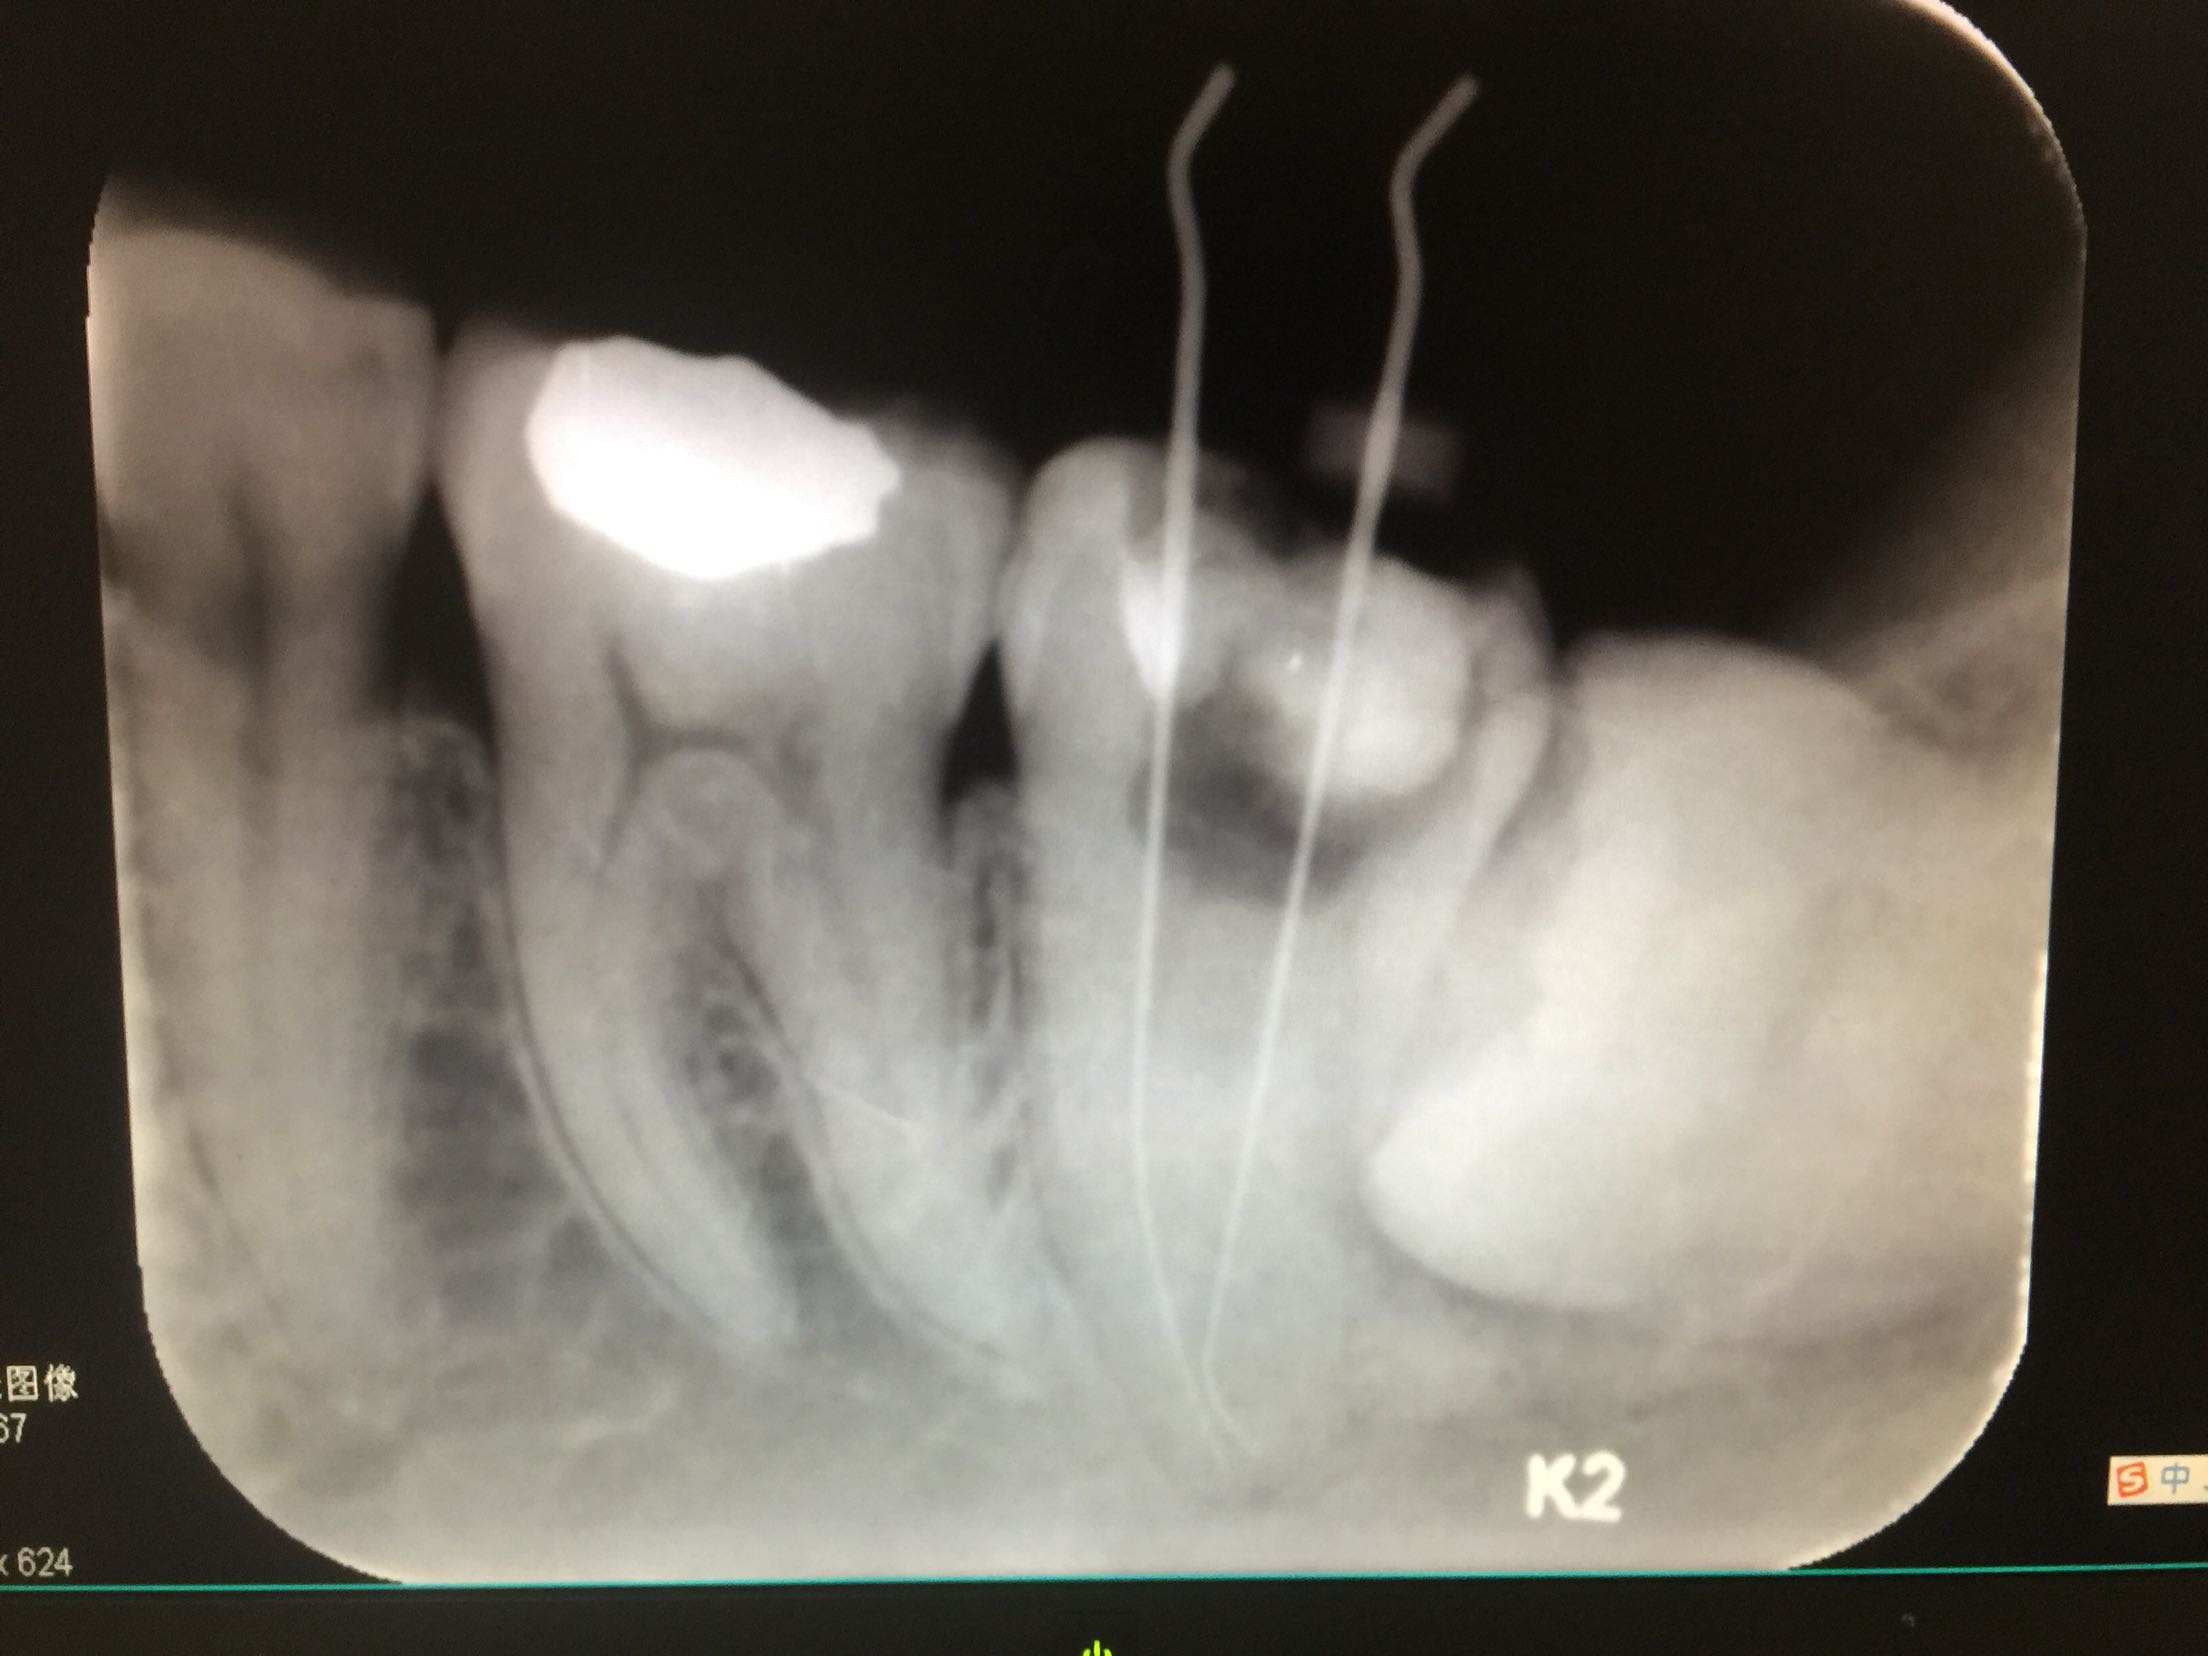

诊断:37牙牙髓炎 18.28.38.48牙阻生齿 治疗计划:18.28.38.48牙拔除 37牙去净原补料及龋坏后视情况制定下一 步治疗计划。 治疗:37牙去净原补料及龋坏后髓室底完整,经患者知情同意,37牙行根管治疗,探查根管口,双根管,冲洗,拍片测长,37牙远中根很尖1/3较弯曲,根管预备时要注意预弯,消毒,根管预备,根管内封进口氢氧化钙,暂封,约复诊。

一周后复诊:诊间无不适,试主尖

热充